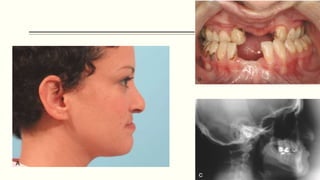

 Malocclusion

 Class III malocclusion, seen in most cases, is caused by many factors.

 Mandibular prognathism - Relative.

 Generally, the operative trauma of the cleft closure and the resultant fibrosis (i.e.,

scar contracture) severely limit the amount of maxillary growth and development

that can take place.

 Orthodontic treatment may be necessary throughout the individual’s childhood and

adolescent years.

 Comprehensive orthodontic care is deferred until later, when most of the permanent

teeth have erupted.

 Nasal Deformity

 Deformity of normal nasal architecture is commonly seen in individuals with cleft

lips.

 The alar cartilage on the affected side is flared

 The columella of the nose is pulled toward the side without the cleft.

 Surgical correction of nasal deformities should usually be deferred until associated

problems have been corrected to prevent alteration of the osseous foundation of the

nose.